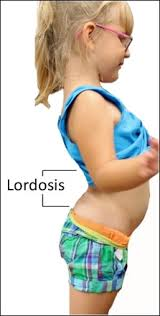

- explain the Lordosis(લોરડોસિસને વ્યાખ્યાયિત કરો).

લૉર્ડઓસીસ મા લમ્બર સ્પાઇનનું કર્વેચર એ ઇન્વાર્ડ કર્વેચર ઇંક્રીઝ થાય છે. તેથી લૉર્ડોસીસ મા સ્વેબેક(સ્વેબેક:= સ્વેબેક એટલે પેલ્વિક એ આગળની તરફ ટિલ્ટ(ઝૂકવું) થાય છે તથા એબડોમન એ બહાર( પ્રોટ્રુઝન) નીકળી જાય છે)જોવા મળે છે.

explain the type of Lordosis (લોર્ડોસીસ સીસના ટાઇપ લખો).

1)સર્વાઇકલ લોરડોસીસ.

આ લોર્ડોસીસ એ સર્વાઇકલ રિજિયન માં જોવા મળે છે.

2)લંબર લોરડોસીસ

આ લોરડોસીસ લંબર રિજિયન મા જોવા મળે છે.

3)હાઇપર લોર્ડોસીસ

આમાં ખૂબ જ વધુ લમ્બર રિજિયન માં ઇન્વાર્ડ કર્વેચર થાય છે.

4)હાઇપો લોરડોસીસ

આમાં ઓછા પ્રમાણમાં લમ્બર રિજિયન મા ઇન્વાર્ડ કર્વેચર થાય છે.

explain the Etiology Of Lordosis (લોરડોસિસ ના કારણ વર્ણવો)

- મેદસ્વિતા ના કારણે. રિકેત્શ.

- પ્રેગનેન્સી.

- ખૂબ વધુ પડતા ફેટના કારણે.

- ઇન્ટરવર્ટીબ્રલ ડિસ્કમાં ઇન્ફ્લામેશન ના કારણે.

- એટ બર્થ ડેવલોપમેન્ટલ એબનોર્માલીટી ના કારણે.

- સ્પોન્ડાયલોલીથીઆસીસ( આમાં લમ્બર રિજિયન મા રહેલા વર્ટેબરા એ આગળ તરફ ફોરવર્ડ થાય છે)

- ઓસ્ટીઓપોરોસિસ ( આમાં બોન એ ફ્રેજાયલ થાય છે).

- એનકોન્ડ્રોપ્લાસિયા( આમાં બોન એ નોર્મલી ગ્રો થતા નથી અને તેના બદલે શોર્ટ રહી જાય છે.)

- એબનોર્મલ પોસ્ચર ના કારણે.

- મસ્ક્યુલર ઇમબેલેન્સ.

explain the Clinical manifestation/sign and symptoms of Lordosis( લોર્ડોસીસ ના લક્ષણો તથા ચિન્હો જણાવો).

- લોરડોસીસ માં સિમટોમ્સ એ તેની સીવીઆરીટી ઉપર આધાર રાખે છે.

- બેક પેઇન.

- મસલ્સ પેઇન.

- “સ્વે બેક” અપિરિઅન્સ.

- લોવર બેક માં ડીસકમ્ફર્ટ થવું.

- મુવમેન્ટમાં પ્રોબ્લેમ થવી.

- નંબનેસ, ટીંગલીંગ સેન્સેશન.

- બોવેલ બ્લેડર કંટ્રોલ લોસ થવું.

- ઉભવામાં તકલીફ પડવી.

- સ્પાઇનલ નવૅમાં કમ્પ્રેશન થવું.

- પગમાં વીકનેસ આવવી.